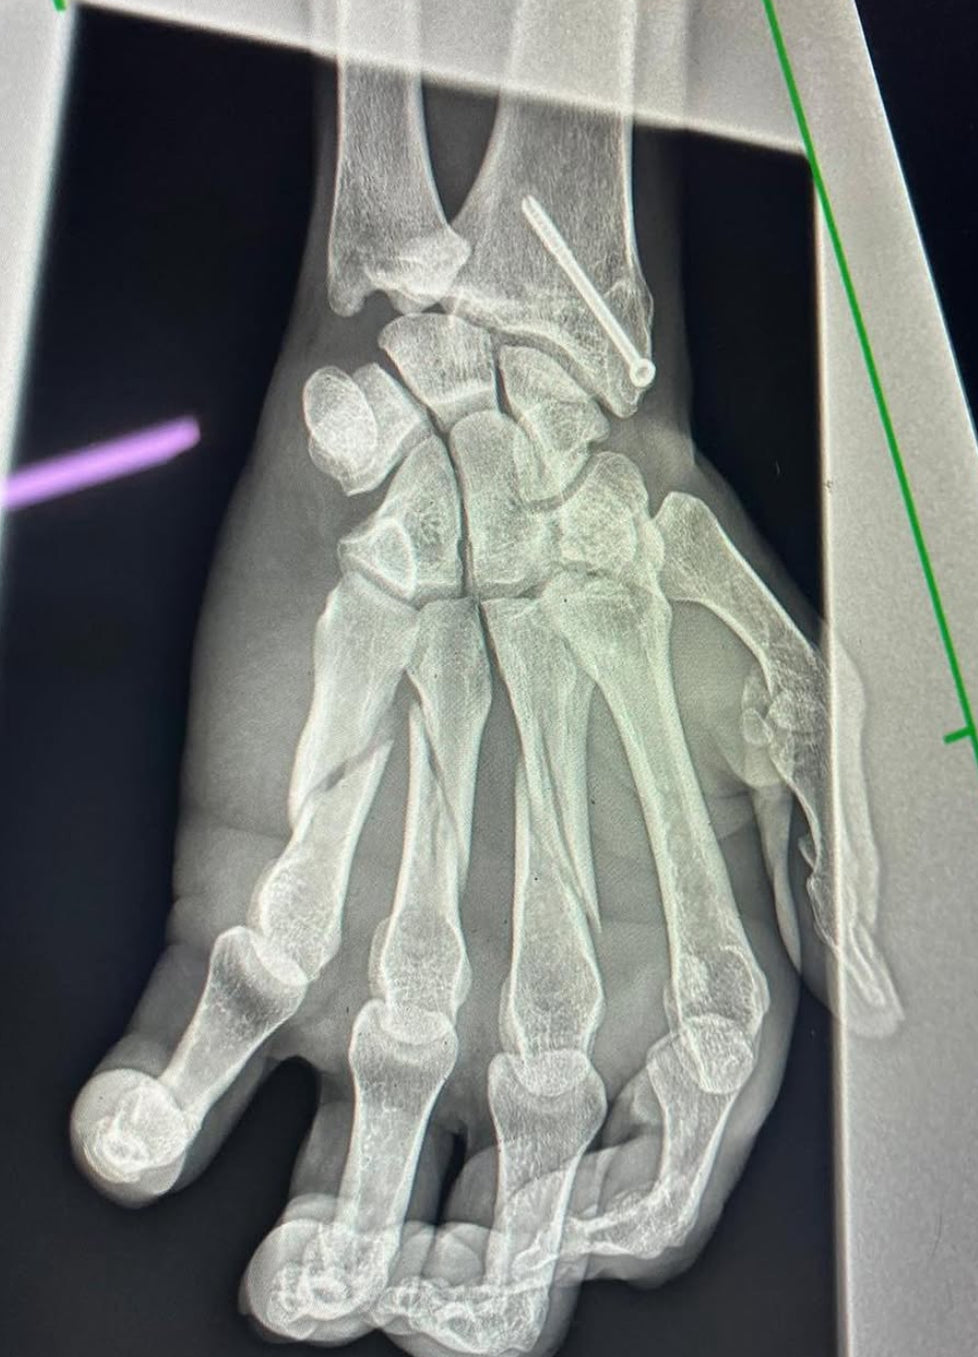

The final of the prestigious British Open Polo Championship – Cowdray Gold Cup this past weekend had it all: drama, family triumph, and the sheer willpower of a living legend. But what turned it from remarkable into unforgettable was this — Adolfo Cambiaso, widely considered the greatest polo player of all time, won the Gold Cup with three broken fingers.

In the closing stages of the match, Cambiaso was involved in a fierce collision with Nicolás Pieres. He hit the ground hard. And although visibly in pain, he refused to leave the game immediately. Only two minutes before the final whistle did he step off the field, allowing a penalty shot that almost cost his team the match.

Despite his injury, Adolfo is not done. He’s already in rehab and focused on returning for Argentina’s upcoming Triple Crown tournaments. It’s still unclear how long the recovery will take — three broken fingers on the hitting hand is no small thing — but if anyone can defy the odds, it’s Cambiaso.

picture : credit Adolfo Cambiaso